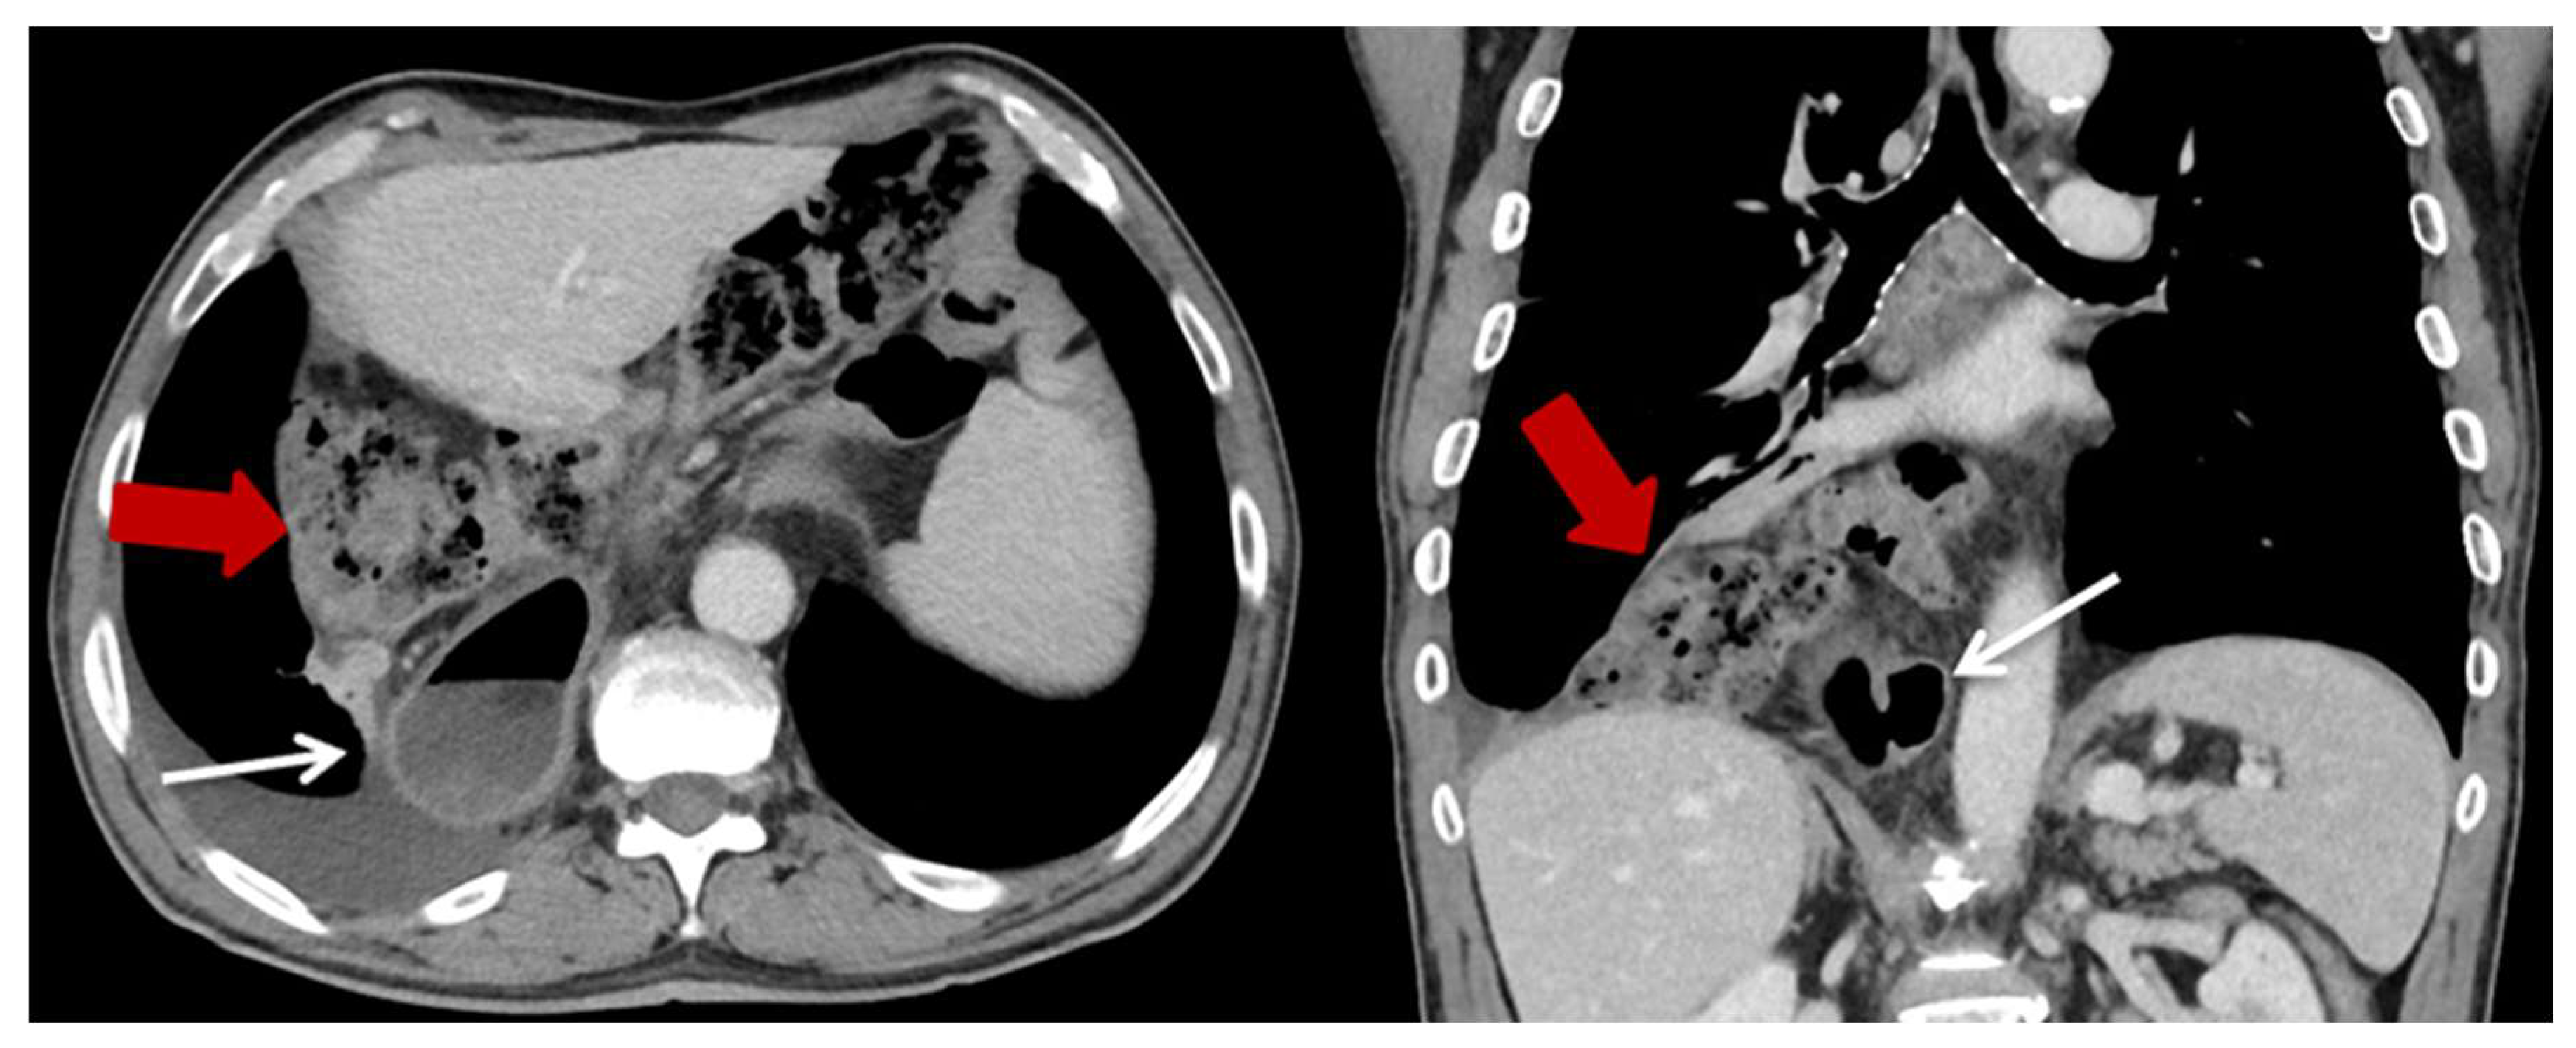

| Characteristics | HH (n = 23) (%) |

| Content of HH, n (%) | |

| Colon | 23 (100) |

| Additionally small bowel | 3 (13) |

| Position of the HH n (%) | |

| Left thoracic side | 18 (78.3) |

| Right thoracic side | 1 (4.4) |

| Both sides | 1 (4.4) |

| Lower mediastinum | 3 (13) |

| Symptoms n (%) | |

| None | 13 (56.5) |

| Abdominal pain and discomfort | 10 (43.5) |

| Ileus/incarceration | 4 (17.4) |